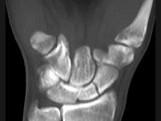

问题 男,21岁,手部不慎摔伤,局部疼痛,结合图像,最可能的诊断是?(?)

选项 A.大多角骨骨折 B.小多角骨骨折 C.三角骨骨折 D.月骨骨折 E.舟状骨骨折

答案 E